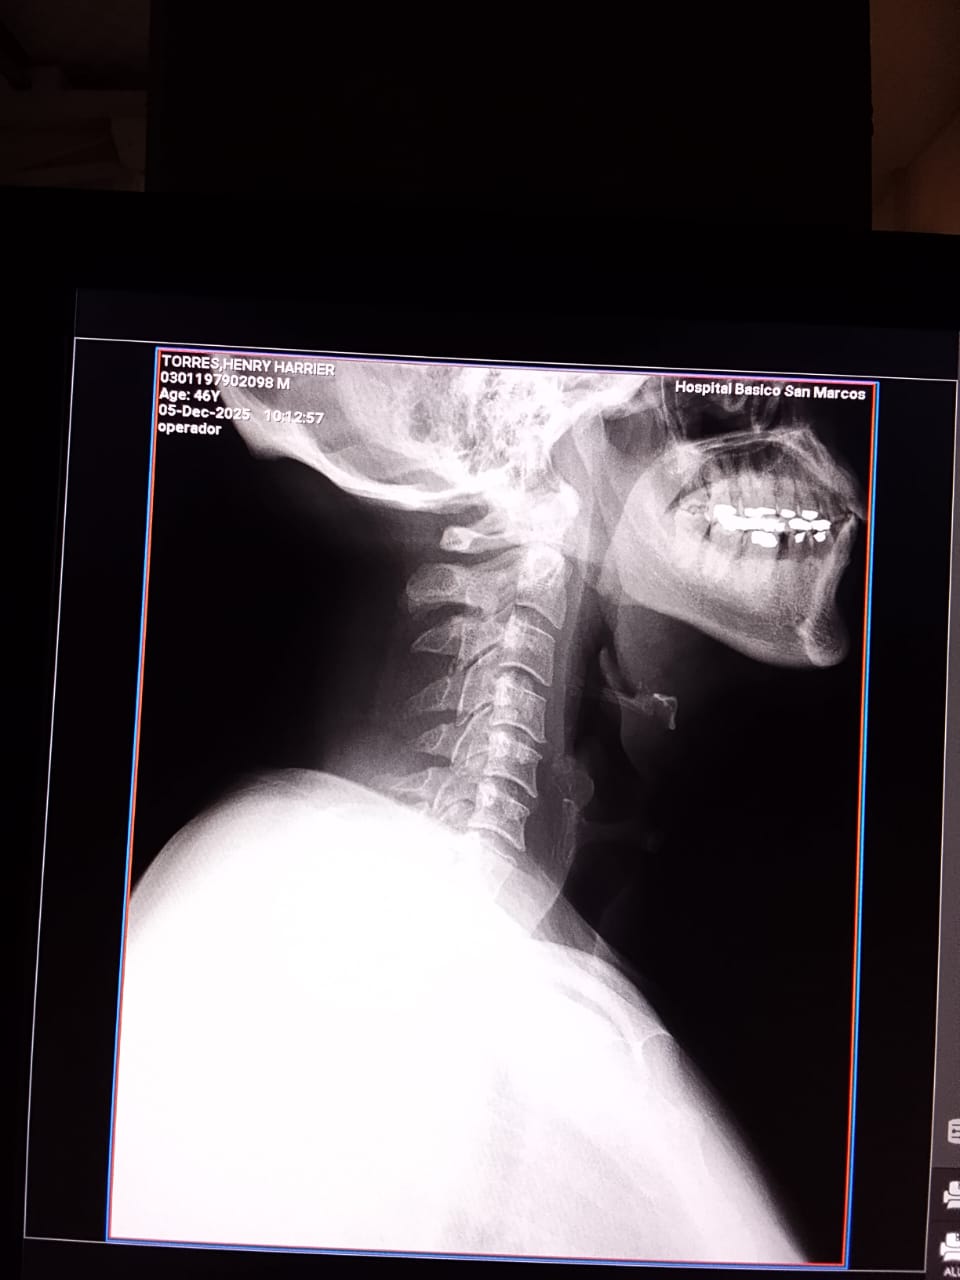

El periodista permanece ingresado en el hospital público local, en estado reservado, sin poder movilizarse debido a las graves lesiones que le ocasionaron. Su esposa, la comunicadora social Nancy Lemus, denunció que este viernes alrededor de las 5:30 p.m., miembros de la Policía Nacional irrumpieron en su vivienda y destruyeron enseres domésticos sin una orden judicial aparente, profundizando la preocupación por un posible patrón de intimidación.